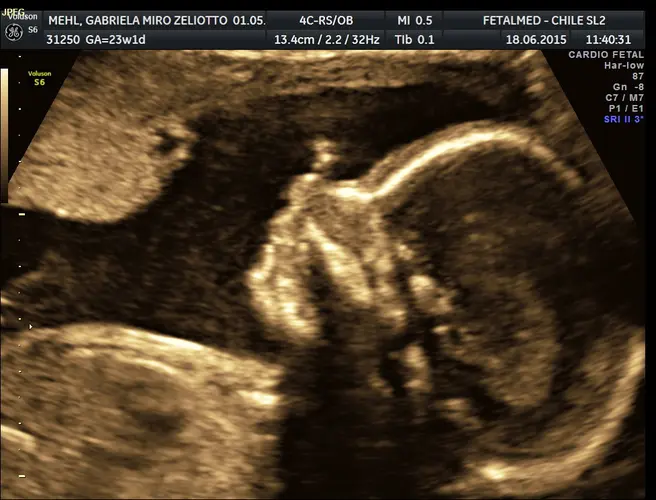

Se você ainda não realizou o ultrassom morfológico de segundo trimestre, esta é uma semana crucial para agendá-lo. Este exame deve ser feito preferencialmente entre 20 e 24 semanas de gestação e é fundamental para avaliar a anatomia fetal e detectar possíveis malformações.

Durante o morfológico, o médico avaliará detalhadamente os órgãos e sistemas do bebê, incluindo coração, sistema nervoso central, rins, coluna vertebral e membros. Também será verificado o crescimento fetal, a quantidade de líquido amniótico e a posição da placenta. Este é frequentemente o momento em que os pais conseguem descobrir o sexo do bebê com mais precisão.